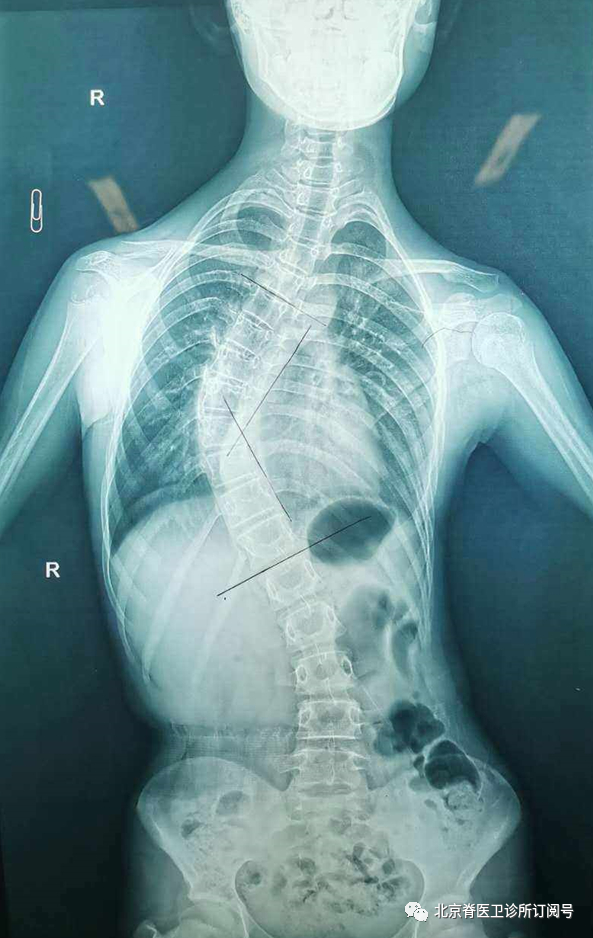

目前,医院常用X光射线检检测脊柱侧弯。

但值得注意的是,上述方式虽然检测速度快、工作量较少,但其辐射面积较大,容易对青少年的血液系统和生殖系统等造成不可逆的损害;同时也因为不便携性和辐射问题,这种方法也不适合对青少年脊柱侧弯情况进行长期随访观察,进而耽误患者及时矫正治疗进程。